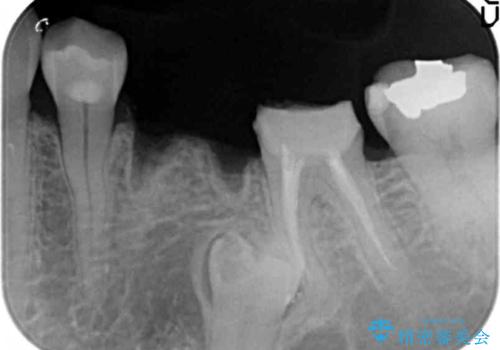

- 大人になってからも残っていた乳歯が揺れ始め、抜歯を覚悟しインプラント治療を希望して来院されました。

X線写真より、乳歯は抜歯が必要な状態でインプラントは小臼歯の埋伏により難しい状況であったのでブリッジによる補綴を選択しました。

ブリッジ治療の予知性を高めるために、虫歯の徹底的な除去に加え縁上歯質を確保するための歯周外科手術、マイクロスコープを用いた精密根管治療を行う治療計画としました。